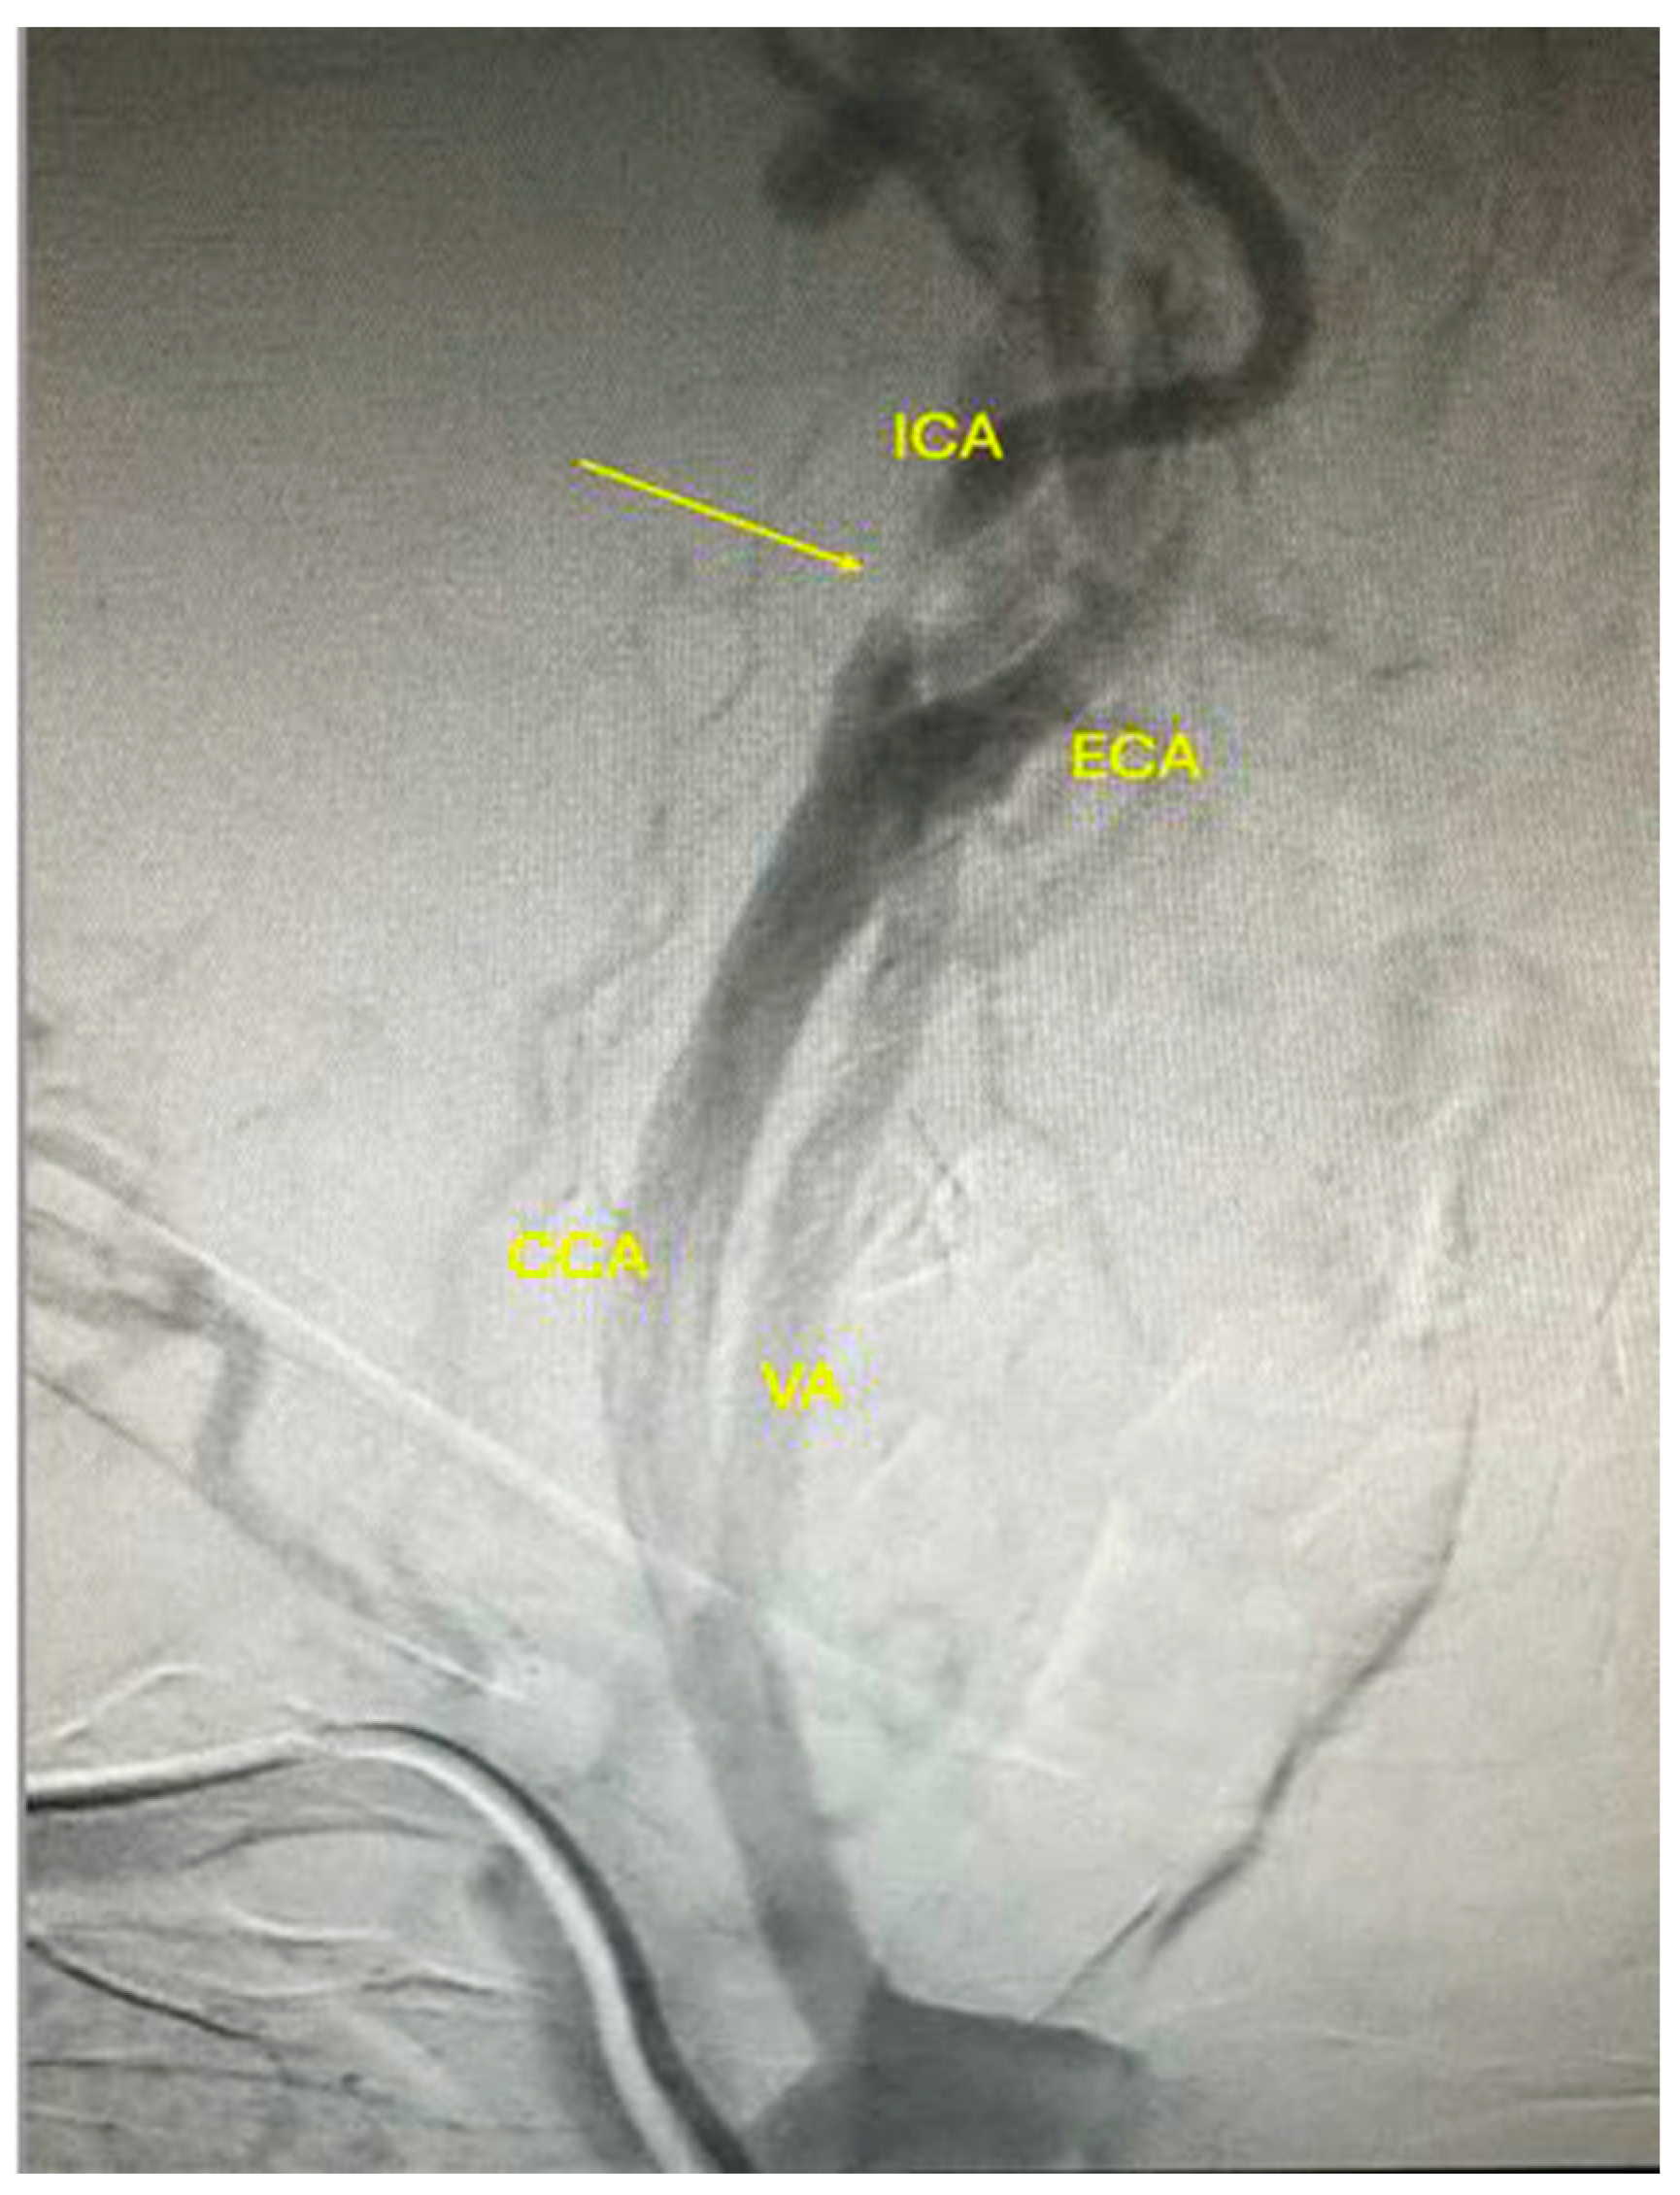

Cervical CT angiography confirmed the severe lesions at the level of the carotid arteries (Figure 2A–C). Additionally, considering the history of ischemic heart disease, coronary angiography was obtained, and carotid angiography was performed in the same setting. Figure 3 shows severe suboclusive stenosis at the level of the left common and internal carotid artery. Unfortunately, the cannulation of the right carotid artery was not possible. Coronary arteries were without any significant stenosis, and the stents at the level of the anterior descending artery were patent.

Figure 3.

Carotid artery angiography showing suboclusive stenosis at the level of the left common and internal carotid artery with patent left vertebral artery. CCA: common carotid artery; ICA: internal carotid artery; ECA: external carotid artery; VA: vertebral artery.